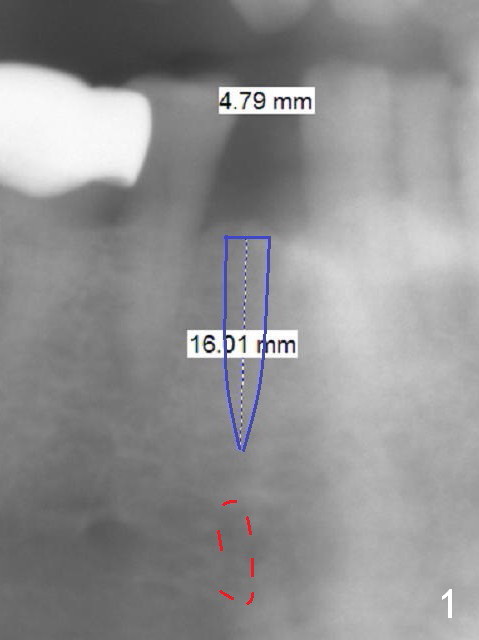

Three weeks post #2 and 4 implantation, the patient requests implantation at #28. If the narrow mesiodistal space (Fig.1 (panoramic X-ray)) is confirmed clinically (using implant positioner), a 3x16 mm 1-piece implant (DIO) will be placed. Also prepare Tatum 3.5 mm 1-piece implant. If there is no space limitation, use an IBS one (4 or 4.5 mm).